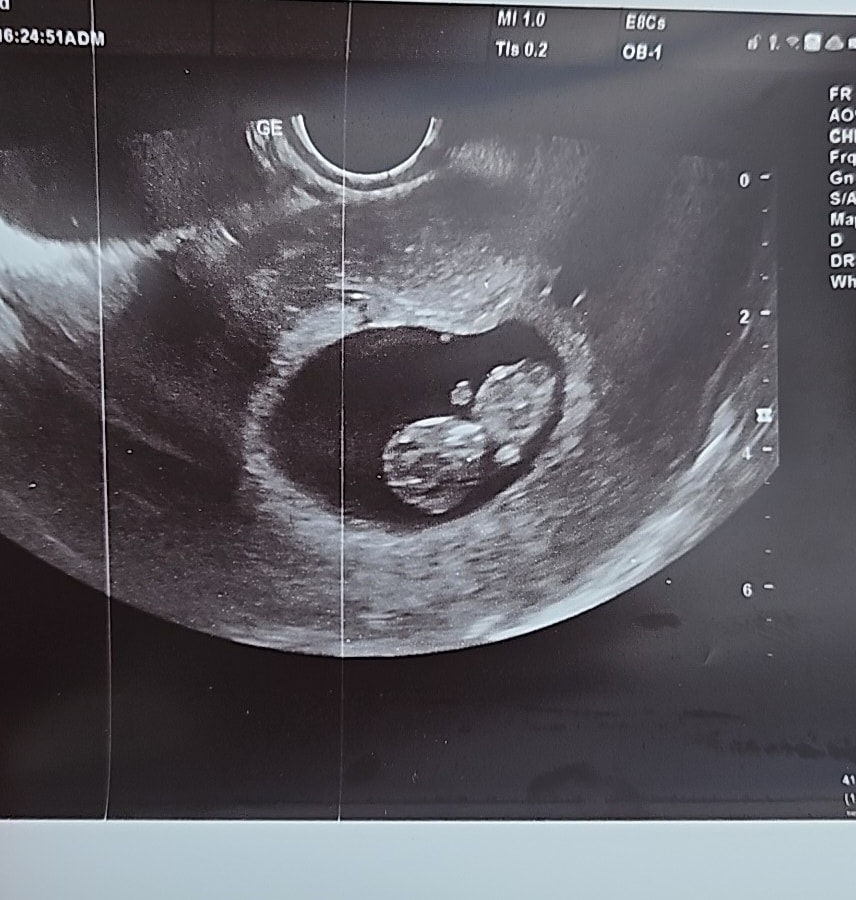

А это сейчас малыш